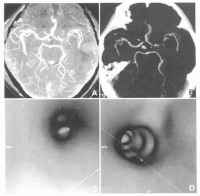

(3)脑血管造影; 颞叶肿瘤的颈动脉造影,主要是以血管移位的情况而作肿瘤的定位,颞叶各部肿瘤的血管移位特点如下:

(1)颞叶前部肿瘤

1)前后位像:大脑前动脉纵行段呈直线向对侧移位,下部移位较明显。大脑中动脉膝段及相连水平段和侧裂段变直,向内上方移位,严重者三段可联成一直线指向上外,使大脑前、中两动脉呈V形。颈内动脉床突上段变直,向内移位。分支抬高。

2)侧位像:大脑前动脉垂直段变直,且向前下方移位。胼胝体膝段曲度张开。中动脉侧裂段变直,向上移位,可在床顶线上1cm以上。颈内动脉床突上段变直、升高与侧裂段呈对角线向上后方走行。侧裂三角前部抬高。额顶升动脉分支变直、分离,也可向上移位。虹吸段可开大。脉络膜前动脉常变直、增粗且向上移位。基底静脉前段可向上向内移位。

(2)颞叶中部肿瘤

1)前后位像:大脑前动脉纵行段呈直线状向对侧移位,移位程度不定,有时较轻。大脑中动脉膝段变直,向内上方移位。轻者只有同对侧比较才能查出,重者则水平段与侧裂段形成一条直线从颈内动脉分支斜向外上,致使与大脑前动脉呈V形。严重时可呈向上内突之弧状。颈内动脉床突上段拉直变长,且向内移位,分支也可抬高。

2)侧位像:虹吸弯开大,甚至可使床突上段呈直线状垂直上升。大脑中动脉侧裂段中部明显上移。侧裂三角抬高。大脑中动脉水平段(M1)可被抬高、拉直与颈内动脉成一直线垂直上升,而与此段相连之侧裂段突然成直角转向后,并呈水平向走行。向上移位的大脑中动脉相当明显,能到达胼周或缘动脉的平面。有时因肿瘤压迫血管可部分闭塞。额顶升动脉也可向上移位。脉络膜前动脉变直、增粗,向内并向上移位。肿瘤如侵犯钩回或其附近,脉络膜前动脉可呈圆弧形突向上。基底静脉向内向上移位。大脑内静脉向对侧移位。